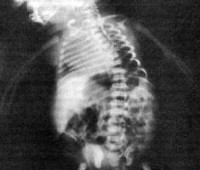

В некоторых случаях диагностику кампомелической дисплазии производят у живого новорожденного. Для этого, помимо вышеуказанных методик, применяют рентгенологическое исследование скелета. На рентгенограммах определяются многочисленные деформации трубчатых костей и другие признаки, которые были выявлены еще на УЗИ. Врачи-неонатологи также могут определить у новорожденного с кампомелической дисплазией порок сердца, аномалии развития почек и респираторные нарушения. Нередко окончательное подтверждение диагноза производится на основании данных патологоанатомического исследования. Практические любые лечебные мероприятия, даже паллиативного характера, при данном заболевании неэффективны и неспособны продлить жизнь больного.